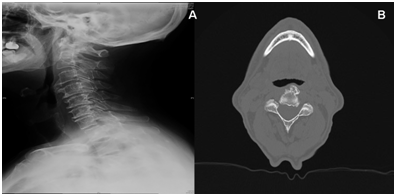

A characteristic radiographic feature of spine involvement is the presence of hyperostosis of the cortex along the anterior surface of the vertebrae (Figure 1). Gradually, elon­gated Osteophytes occur at the anterior margin of the vertebrae and grow across the disc space. Dysphagia from cervical osteophytes (usually located in the anterior and lateral regions of the vertebral bodies) has ranged from C3 to C6. Osteophytes originating from the level of the fifth and sixth cervical vertebrae are usually the ones implicated in this symptom.2

Figure 1A: Lateral cervical X-Ray image B: CT axial view; both showing hyperostosis of the cortex along the anterior surface of the vertebrae. Gradually, elon­gated osteophytes occur at the anterior margin of the vertebrae and grow across the disc space.